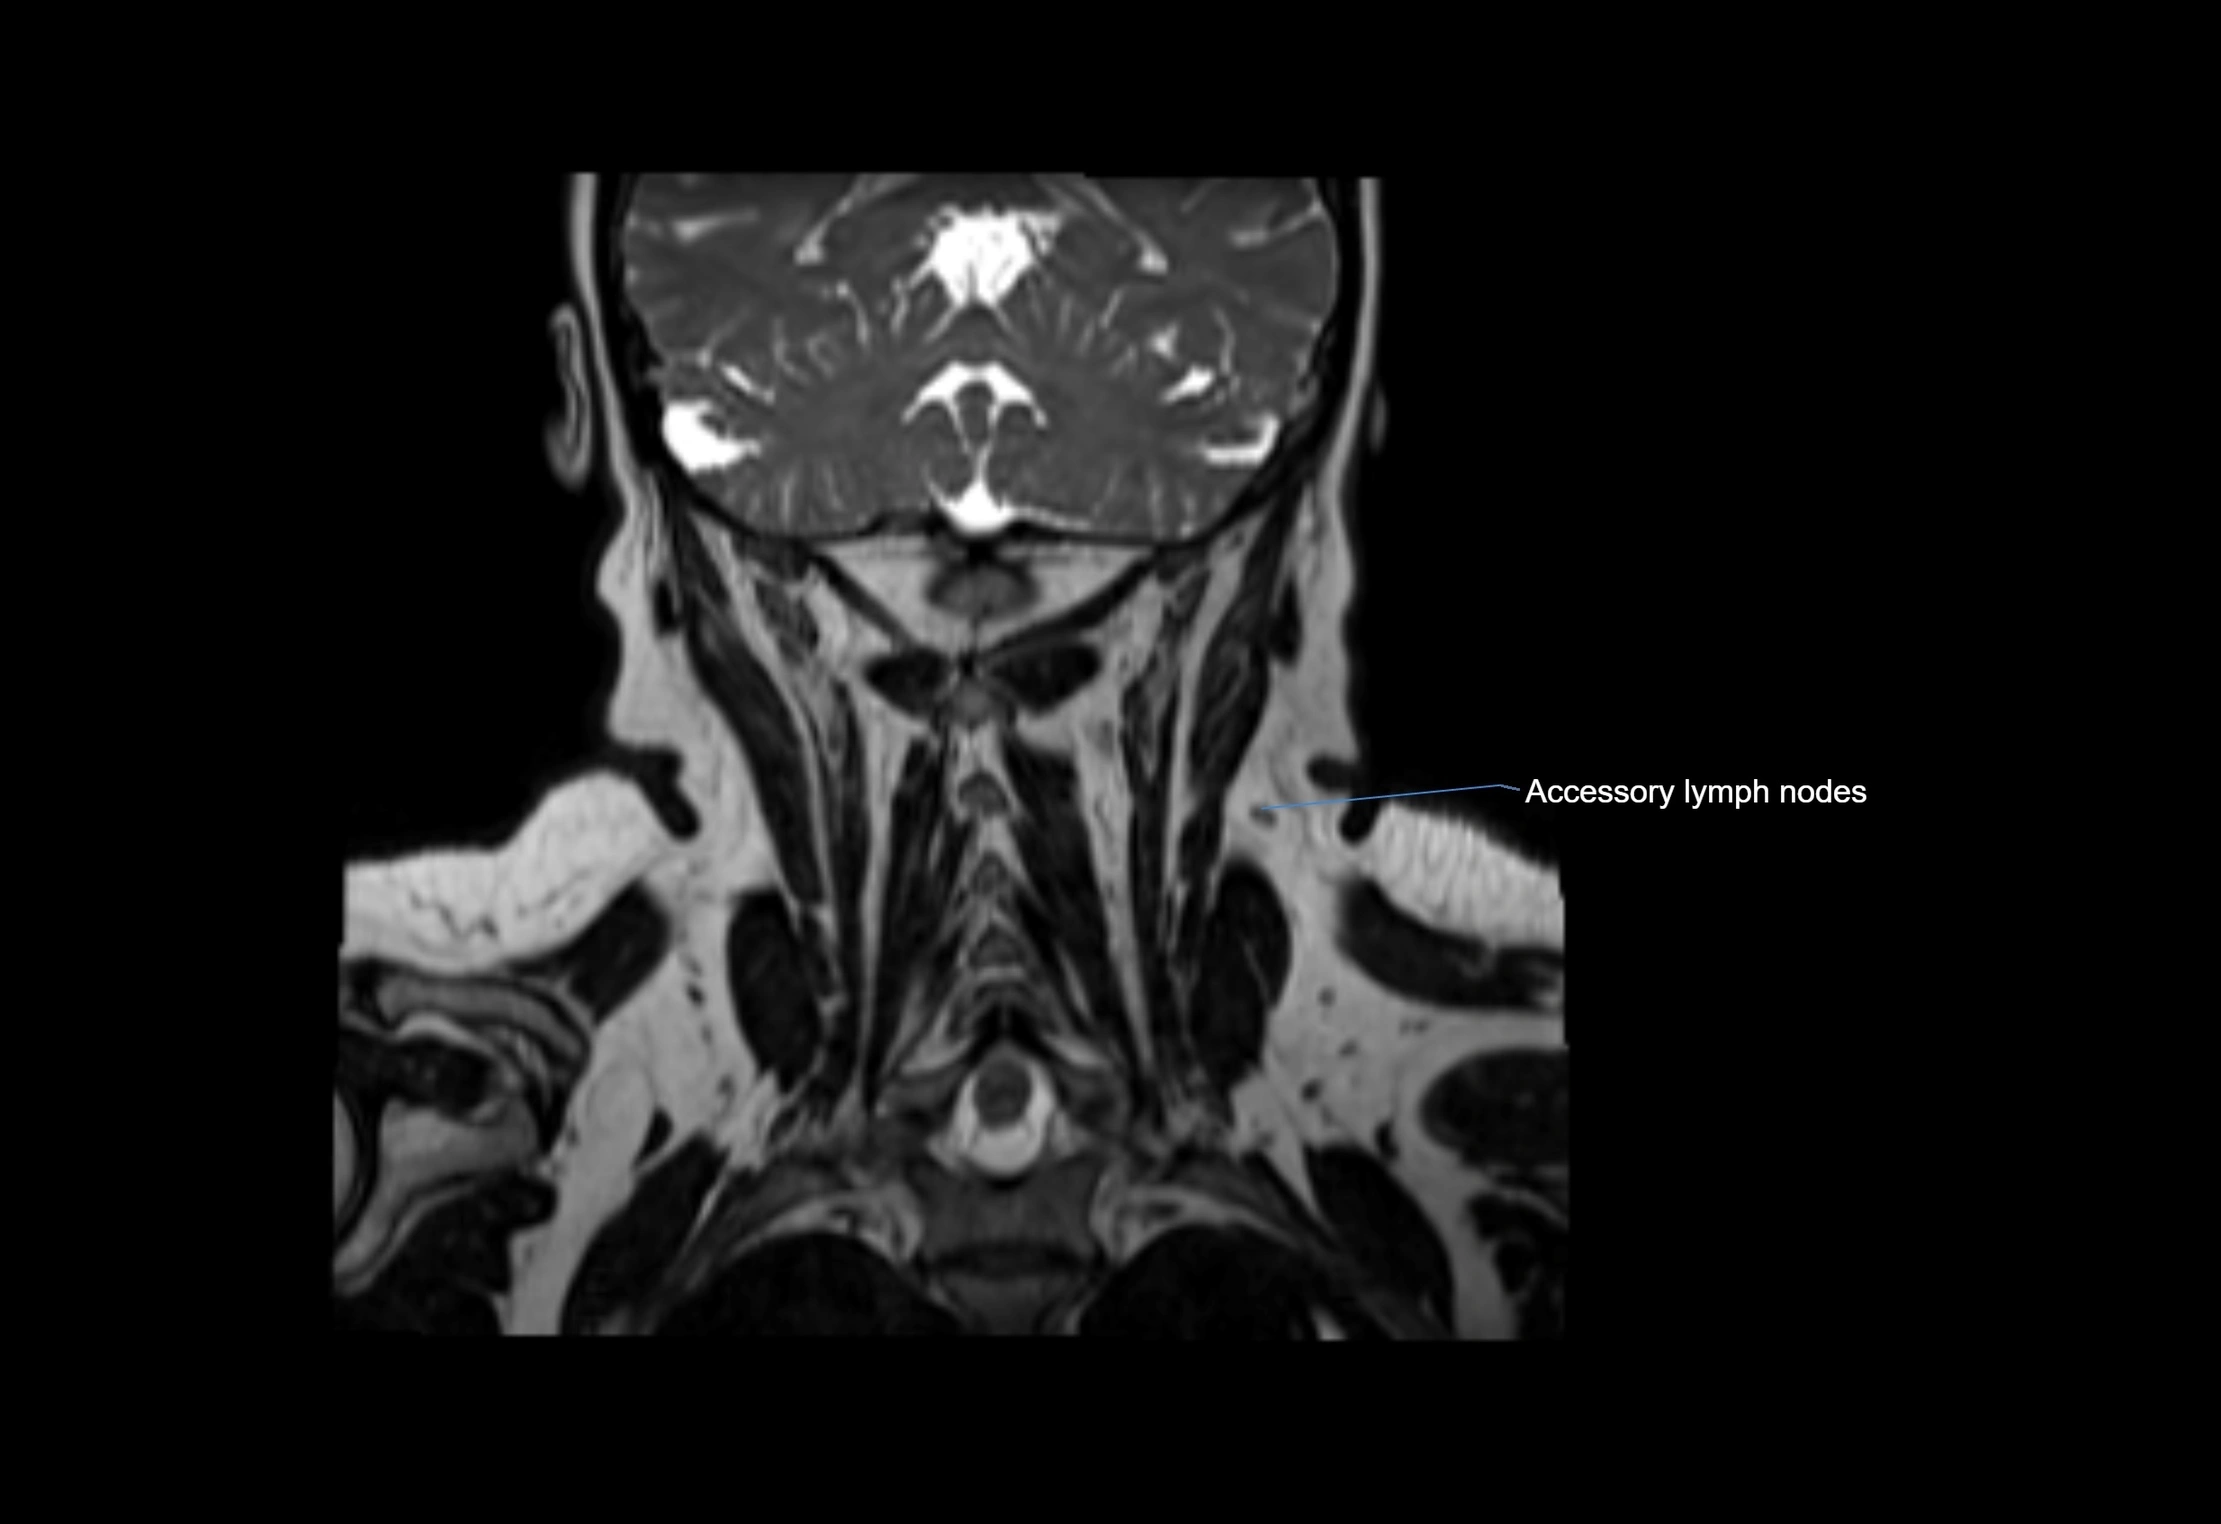

Accessory lymph nodes

Accessory lymph nodes are small, secondary lymph nodes located along the main facial and cervical lymphatic chains, often adjacent to primary lymph nodes, such as preauricular, submandibular, or occipital nodes. They are typically less than 5 mm in diameter, embedded within subcutaneous fat or connective tissue, and may be variable in number and location. These nodes provide additional filtration and immune surveillance for lymph collected from the face, scalp, and neck regions. Accessory lymph nodes are usually non-palpable in healthy individuals but may enlarge in response to infection, inflammation, or metastasis, making them clinically significant.

Location

• Found along primary lymph node chains, including preauricular, submandibular, parotid, and occipital regions

• Embedded in subcutaneous fat or superficial fascia, often lateral or posterior to primary nodes

• Variable in number; may occur unilaterally or bilaterally, depending on individual anatomy

MRI images

image